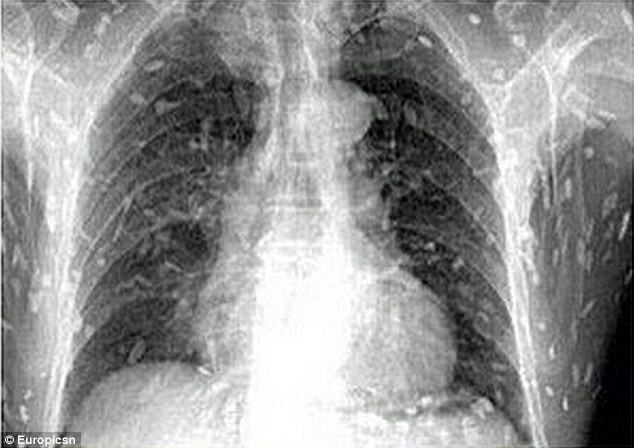

2017年07月17日前幾天,廣東一名男子腹痛難忍,皮膚搔癢,去當地的醫院求診。醫生為他拍X光片檢查,結果在X光片上看到了密密麻麻的白色斑點。大家倒吸一口冷氣,最後才確定,這些全都是絛蟲!

▼醫生提醒民眾,吃生魚片、生豬牛肉都可能感染,一些魚塘的淡水魚更加危險。因為魚塘裡的魚很容易被污染,沾上糞便。感染絛蟲後非常麻煩,如果這些絛蟲在肌肉外圍,只要驅蟲就能解決問題。如果已經侵入腦部,就可能變成腦囊蟲病,最後引發腦水腫,還會危及生命。

之前也有報導稱,鮭魚生魚片中含有日本海裂頭絛蟲,吃下肚後非常危險。不過大家不用太擔心,因為吃生魚片感染寄生蟲的案例,在台灣比較少見。反而是吃沒煮熟的豬肉、沒有妥善處理的淡水魚生魚片,感染絛蟲的機率比較高。如果感覺不舒服,一定要儘快就醫,只要早發現,醫生會幫忙「殺蟲」的~